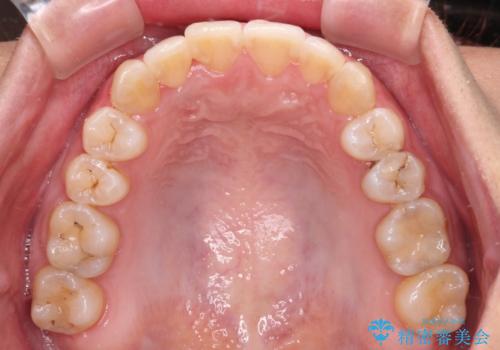

前歯のデコボコをインビザラインでスッキリと仕上げる

- 上下前歯のデコボコと奥歯の銀歯を気にして来院された患者様です。

口元をインビザラインにより歯列を整え、その後に失活している奥歯をオールセラミッククラウンにて補綴治療することとしました。

長時間のマウスピース装着に協力いただき、自然な口元に仕上げることができました。

気になっていた銀歯もオールセラミッククラウンで本物の歯のようになり、患者様には大変満足していただきました。